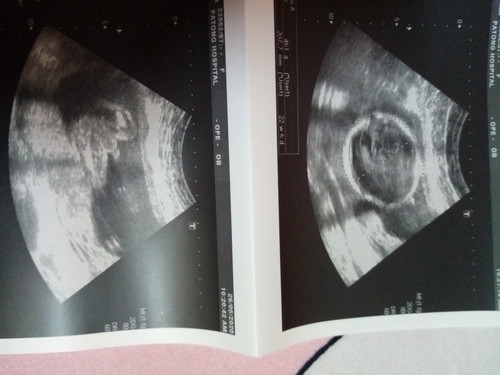

22week 5day ผู้ชายคะ

ท้องก็จะโตไปหน่อย